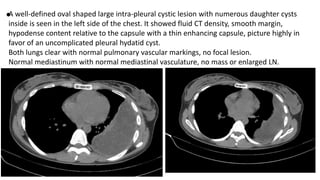

•A well-defined oval shaped large intra-pleural cystic lesion with numerous daughter cysts

inside is seen in the left side of the chest. It showed fluid CT density, smooth margin,

hypodense content relative to the capsule with a thin enhancing capsule, picture highly in

favor of an uncomplicated pleural hydatid cyst.

Both lungs clear with normal pulmonary vascular markings, no focal lesion.

Normal mediastinum with normal mediastinal vasculature, no mass or enlarged LN.